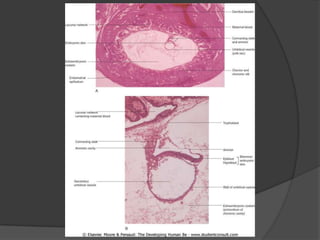

Durante a segunda semana, o tampão cobre o epitélio do endométrio, o sinciciotrofoblasto produz hCG, e forma-se a cavidade amniótica e o embrioblasto. O mesoderma extraembrionário forma o saco vitelino definitivo e o celoma extraembrionário, enquanto o saco coriônico desenvolve vilosidades coriônicas. Ao fim da semana, a placa pré-cordal se forma.